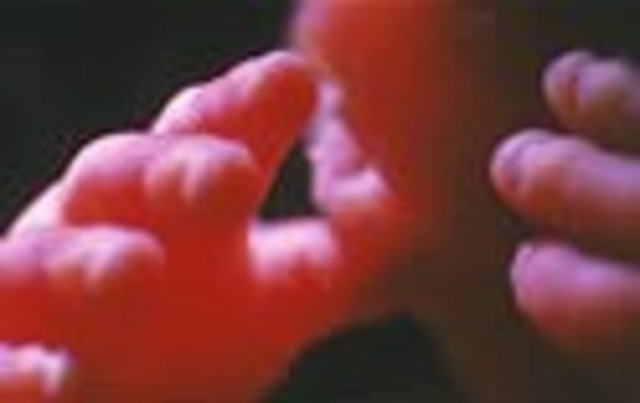

• Week Twenty Five

Week Twenty Five

The fetus's hands are now fully developed and it expores the uterus. If there are twins, then they explore each other.

• Week Twenty Six

Week Twenty Six

This is about the time when the fetus becomes most active. The fetus's hands are active and muscle coordination is such that it can suck its thumbs.